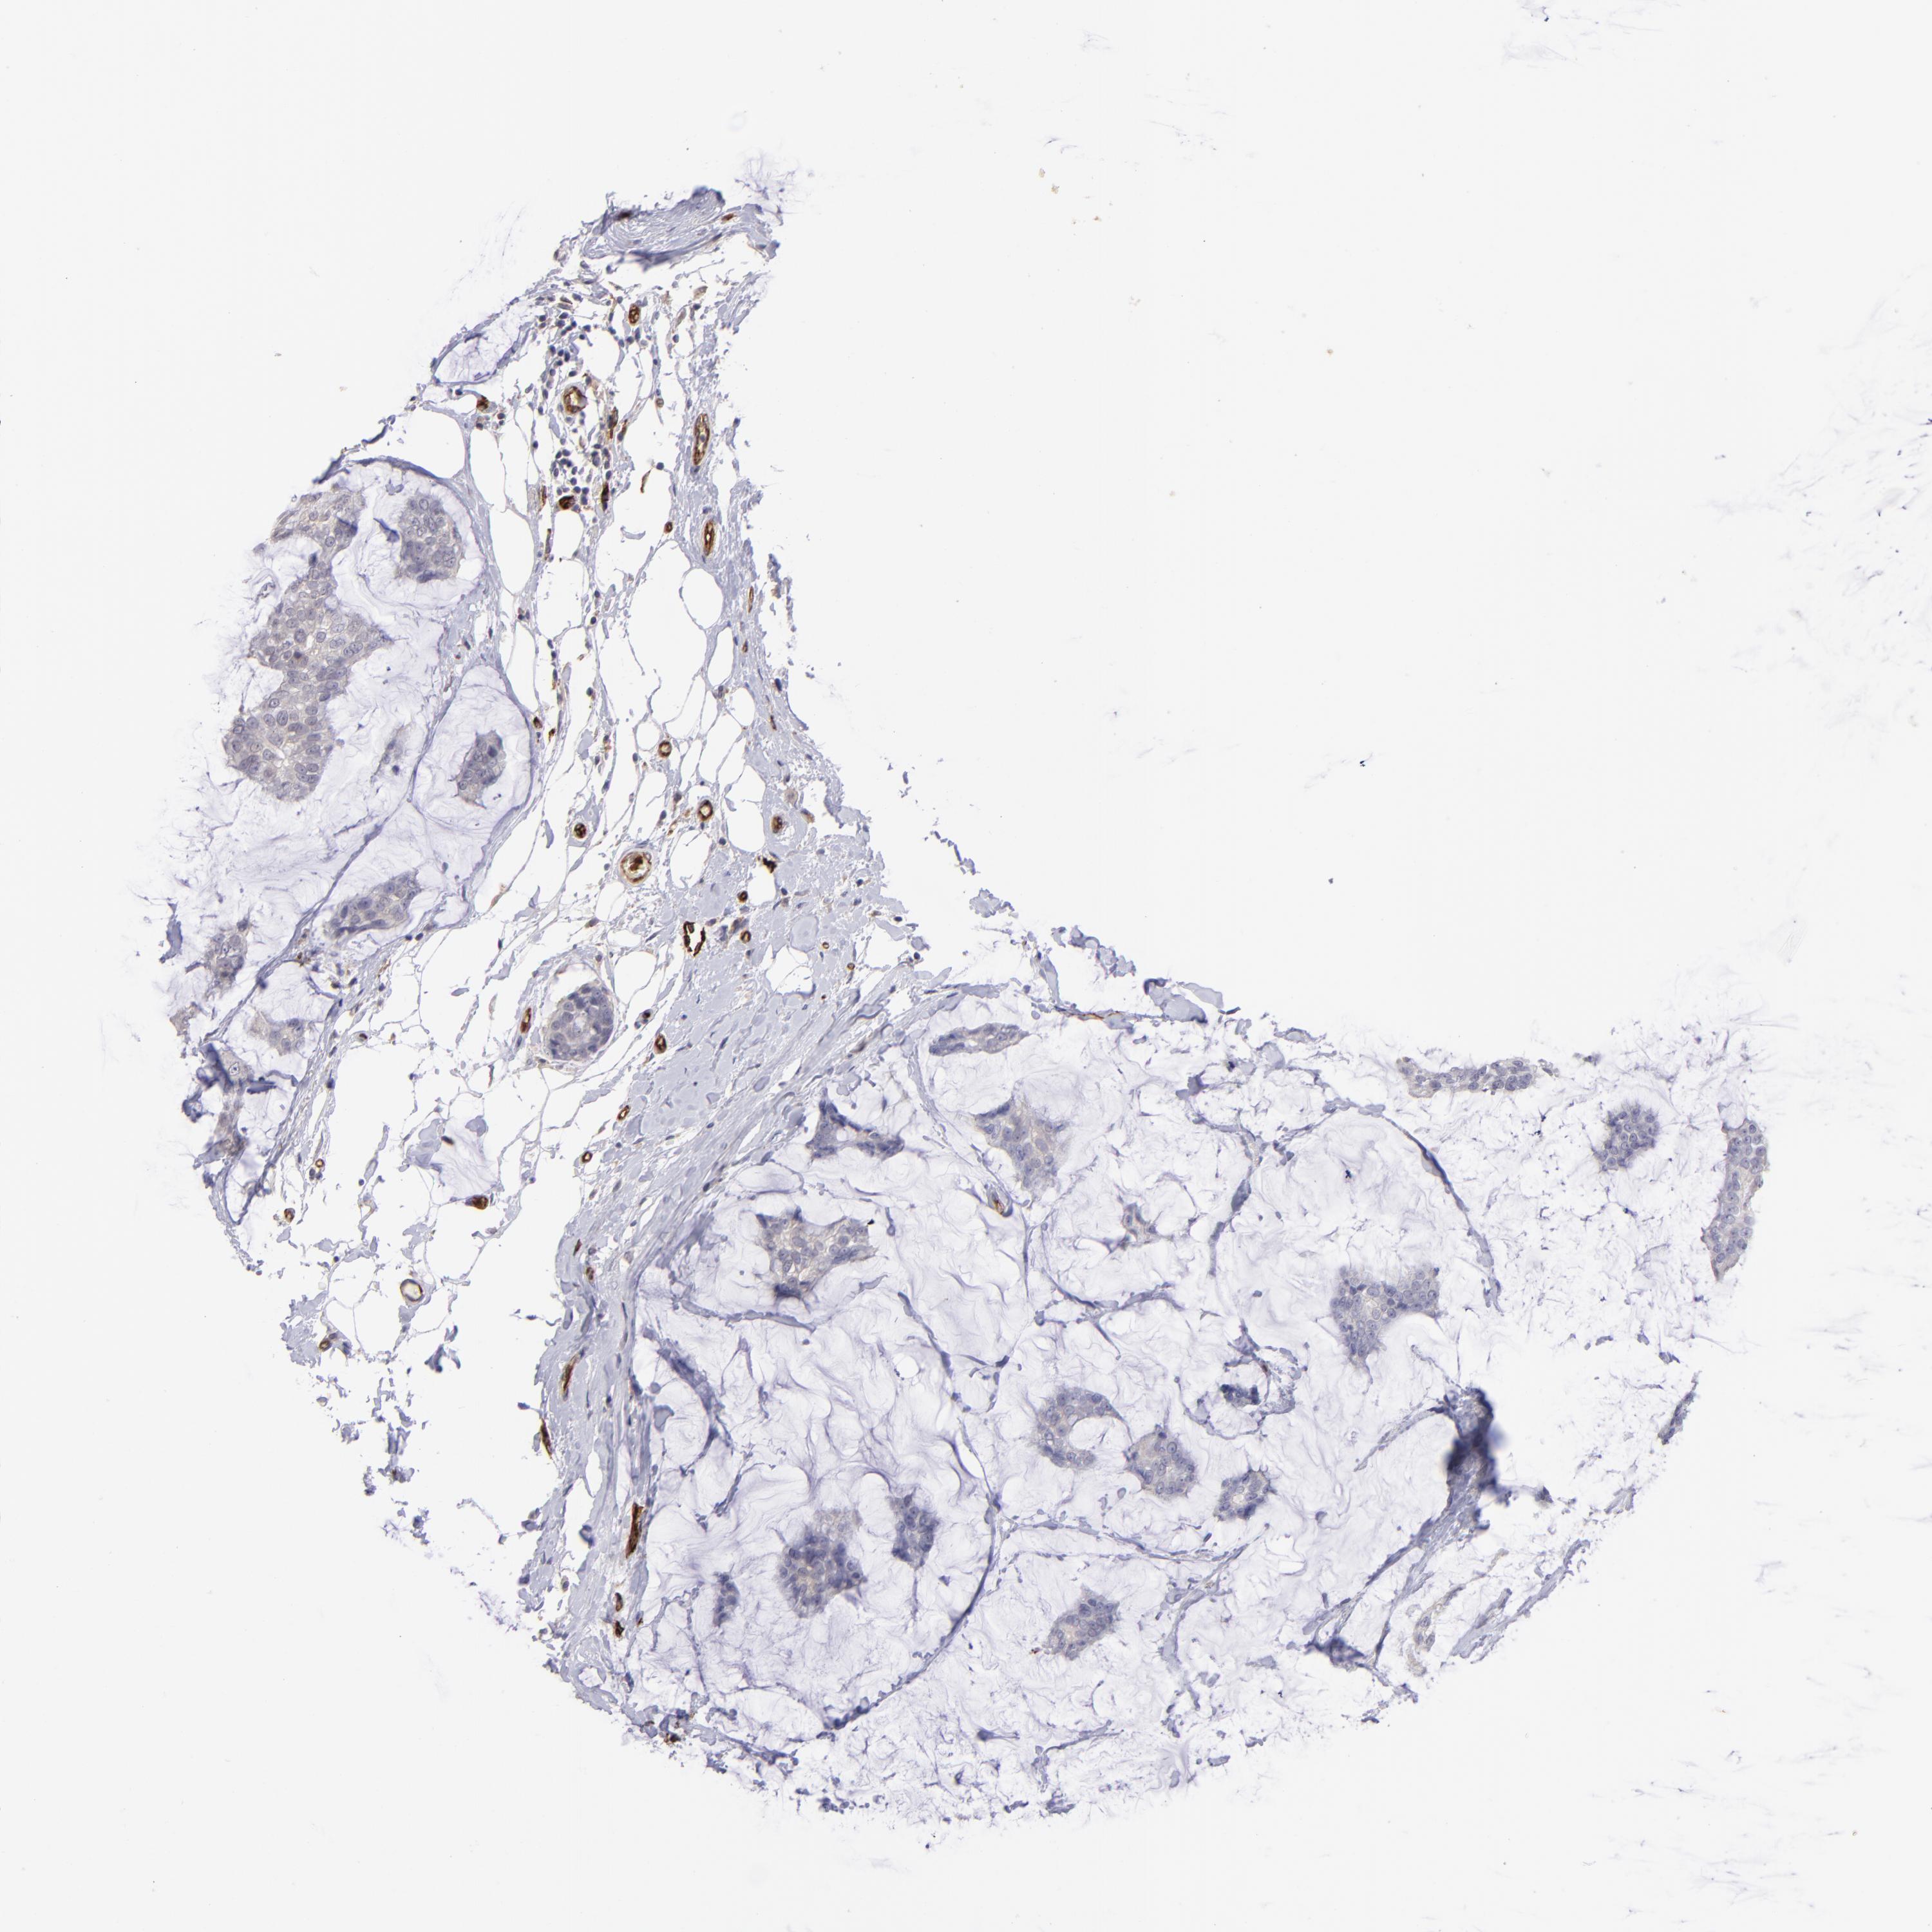

BRCA TCGA BRCA VALIDATION PROTEIN EXPRESSION